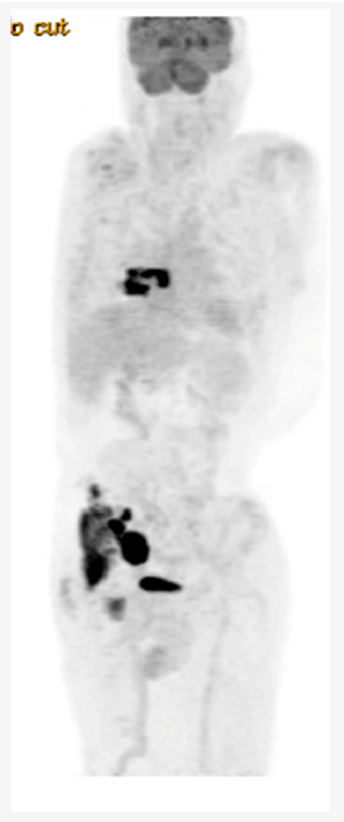

Key clinical features â˘â58 -year-old male â˘âNo comorbidities â˘âPresented with abdominal discomfort â˘âECOG PS 1 â˘âLabs: LDH 350 U/L (ULN 240) â˘âPET/CT: paravertebral soft tissue mass at T7 with extension into right lower lobe, right pelvic sidewall mass (maximum 6 cm) Diagnosis â˘âCore biopsy of abdominal mass: DLBCL, GCB subtype, no MYC rearrangement Initial Treatment â˘âTreated with 6 cycles of R-CHOP â˘âCR on post-treatment PET/CT â˘â14 months later, developed recurrent abdominal pain, PET/CT and biopsy confirmed recurrent DLBCL Second-line Treatment â˘âPlanned for salvage and ASCT, but had progression after 2 cycles R-GDP Third-line Treatment â˘âReferred for CAR-T-cell therapy â˘âReceived 1 cycle Pola-R bridging followed axicabtagene ciloleucel â˘âCR on PET/CT at 3 months â˘âProgression on PET/CT at 6 months post CAR-T-cell therapy Fourth-Line Treatment â˘âHe has been recently given epcoritamab |

- Unfortunately, this otherwise healthy man, exhibits chemo-refractory disease after initial benefit from R-CHOP and did not sustain durable benefit from CAR-T cell therapy.

- BsAbs have demonstrated efficacy for patients with R/R DLBCL regardless of prior exposure to CAR-T cell therapy. [1,3] This case illustrates the potential use of BsAbs following CAR T-cell therapy failure, with CAR T-cell therapy initially prioritized due to its longer available follow-up and known curative potential.